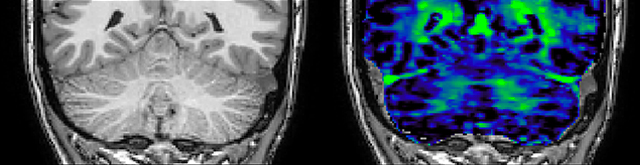

T1 - weighted

Myelin water imaging - T1 weighted

Myelin water imaging (echo 1)

Myelin water imaging with SENSE

Myelin water imaging with Compressed SENSE

T1 - Weighted, Myelin Water Fraction Superimposed

MWI Spinal cord coverage

Spinal cord coverage

MWI Smaller, more isotropic voxels

Smaller, more isotropic voxels

MWI Excellent detail in quantitative maps

Excellent detail in quantitative maps

Images courtesy of Adam Dvorak, Department of Physics and Astronomy, University of British Columbia

20%

Myelin water fraction

0%